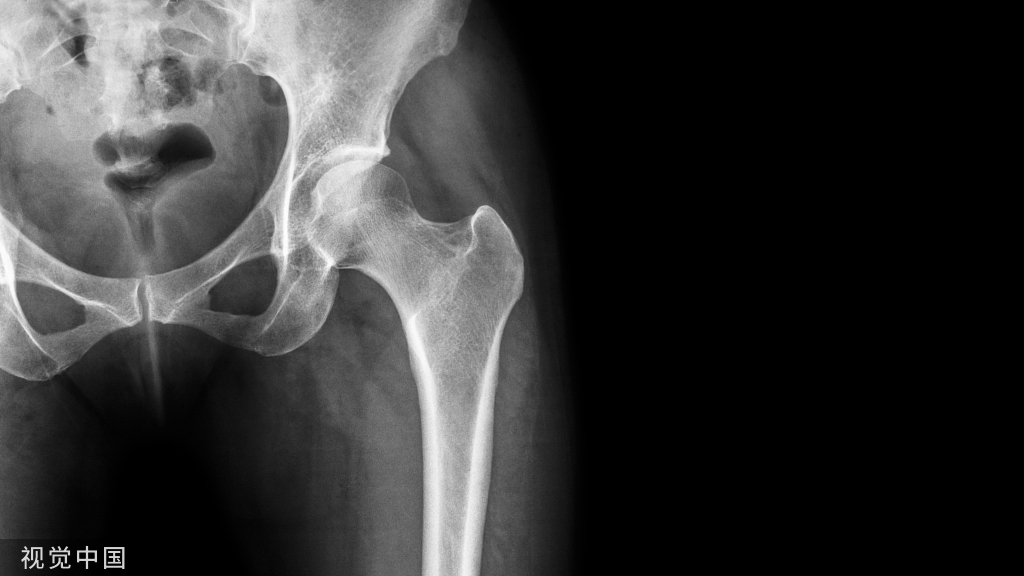

髁状突颈部越粗,说明下颌骨发育越好;越细,说明下颌骨发育越差。